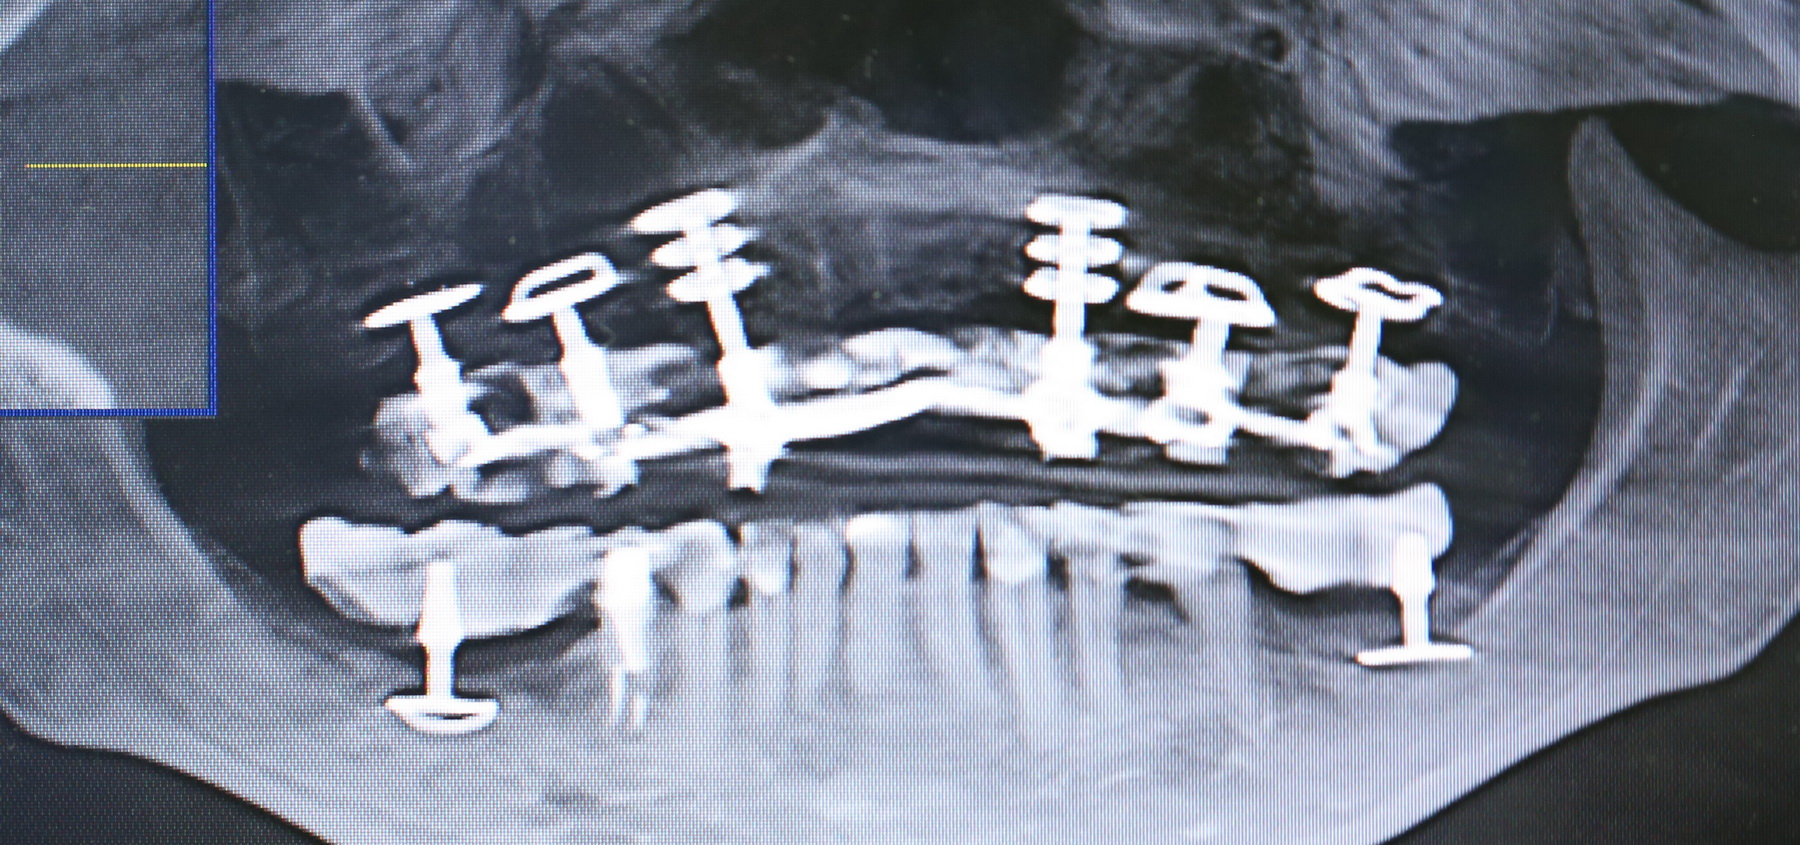

А теперь посмотрите снимок этого пациента:

Как вы считаете, что будет травматичнее и опаснее: установка шести имплантов такой формы или два простых синуслифтинга и шесть обычных имплантов?

К слову сказать, базальные импланты не интегрируются, а удерживаются, исключительно, за счет своей формы:

А это значит, что длительная функциональная нагрузка в таком объеме просто будет их медленно расшатывать. Особенно, если учесть, что их нагружают почти сразу после установки. И весьма большой протетической конструкцией.